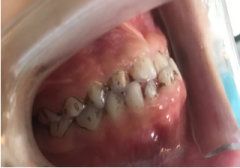

孩子牙齿正常后这个妈妈坚信:“地包天”矫正真要尽早!

随着观念的改变 很多新一代的父母 往往对孩子的口腔健康 给予更多的关注 所以能够更早地发现 孩子的口腔...